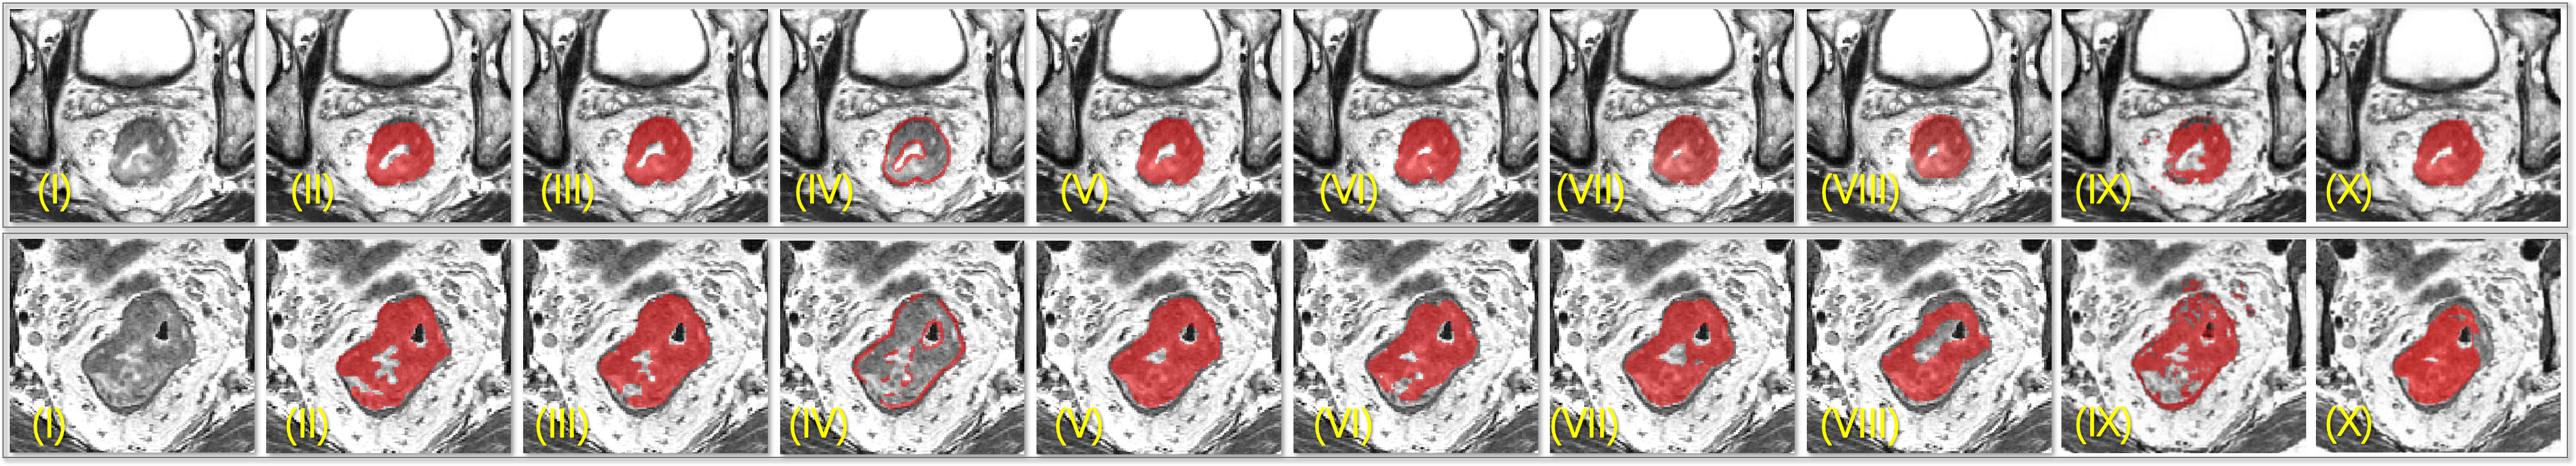

For evaluation, four-fold cross-validation was conducted on 64 scans and their mean scores are reported in TABLE. 2. Comparison of predicted masks between different methods is illustrated in Fig. 5; Eight volume predictions are illustrated in Fig. 6.

Although our method achieved competitive results, there are some limitations. Firstly, as is illustrated in Fig. 6, the model is often confused about which slice to start or end, thus this significantly affects the score. As is illustrated in TABLE. 2, all competing methods including applying a bidirectional convolutional LSTM [16] did not thoroughly tackle this issue. As an explanation, this difficulty is data-related and decision about starting and ending slice index can be observer-dependent due to weak contrast in the border of cancerous tissues and low resolution along Z axis. Secondly, for this specific task without the need of discriminating different instances of tumors, we did not include instance separation capability in our design. However, it can be addressed since that the RoI Locator is a template that any encoder-only detection method is applicable, yet it can still be beneficial to fully utilize voxel-wise labels for bounding box refinement.